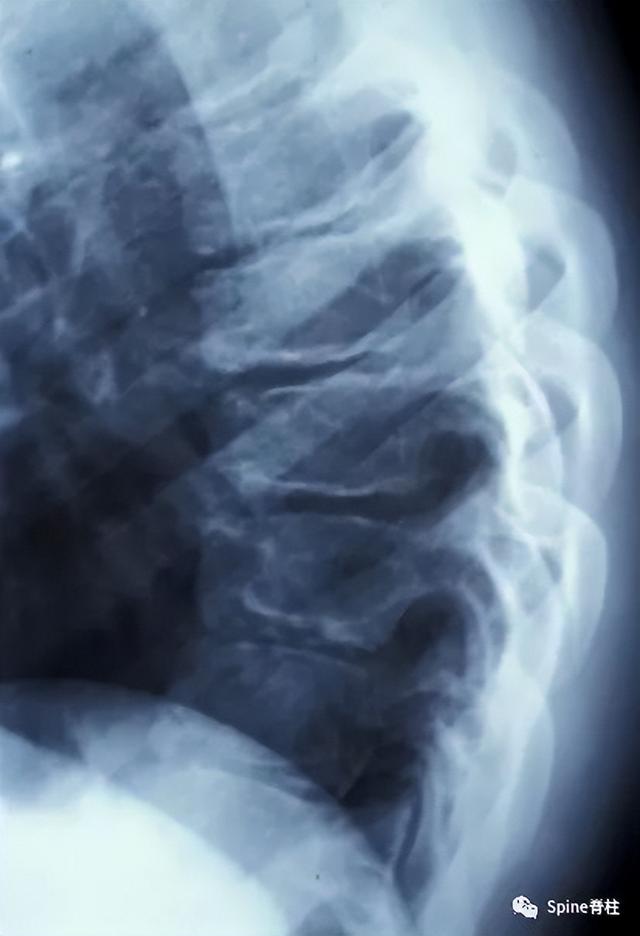

休门氏病(青少年驼背最常见病因)的影像表现与临床

的僵硬型脊柱后凸(驼背)畸 形,称为休门 (scheuermann) 氏病

scheuermann病(休门氏病)

胸腰段椎体休门氏病所致脊柱后凸畸形一例